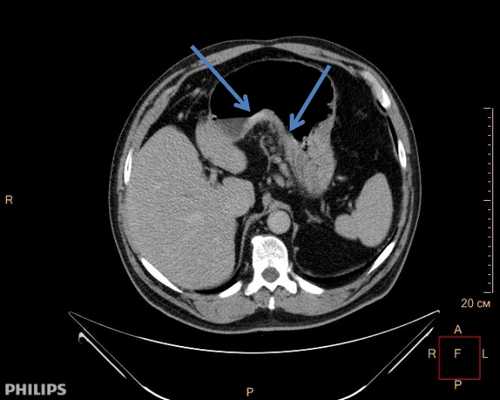

- КТ грудной полости покажет локализацию метастазов в лимфоузлах и вовлечение в конгломерат соседних структур.

- КТ брюшной полости поможет найти метастазы.

• Компьютерная томография(КТ) – метод, основанный на рентгеновском излучении. Источник рентгеновского излучения и датчик вращаются вокруг пациента. За каждую секунду аппарат делает множество снимков с разных углов. Данные обрабатываются компьютером, который строит изображения внутренних органов. На полученных картинках можно рассмотреть детали размером до 1 мм. При раке пищевода КТ позволяет определить границы поражения пищевода, выявить пораженные метастазами органы и лимфатические узлы, а также заподозрить врастание в соседние органы.

3. КТ рака пищевода:

• Утолщение стенок пищевода:

о Асимметричное или циркулярное

о Не позволяет дифференцировать опухоли на стадии Т1, Т2 и Т3

о Сохранность жировой клетчатки между опухолью пищевода и прилежащими структурами средостения исключает стадию Т4

• Изолированное объемное образование пищевода

• Местная инвазия (Т4):

о Отсутствие жировой клетчатки между пищеводом и аортой или позвоночником

о Трахеоэзофагеальный или бронхоэзофагеальный свищ

о Смещение дыхательных путей, вдавление на их стенках или рост опухоли в их просвет

о Утолщение перикарда, перикардиальный выпот, отсутствие жировой клетчатки между перикардом и пищеводом/опухолью

о Охват аорты на протяжении >90°

• Мультипланарная реконструкция изображений облегчает определение протяженности опухоли в краниокаудальном направлении, что необходимо для планирования хирургического вмешательства или лучевой терапии

• Лимфаденопатия:

о Размер внутригрудных и брюшных лимфатических узлов > 1 см по короткой оси

о Размер надключичных лимфатических узлов>5 мм по короткой оси

о КТ не обладает высокой чувствительностью или специфичностью

• Метастазы:

(а) У пациента с аденокарциномой пищевода при КТ с контрастным усилением определяются циркулярное утолщение стенок дистальных отделов пищевода и увеличенный правый параэзофагеальный лимфатический узел.